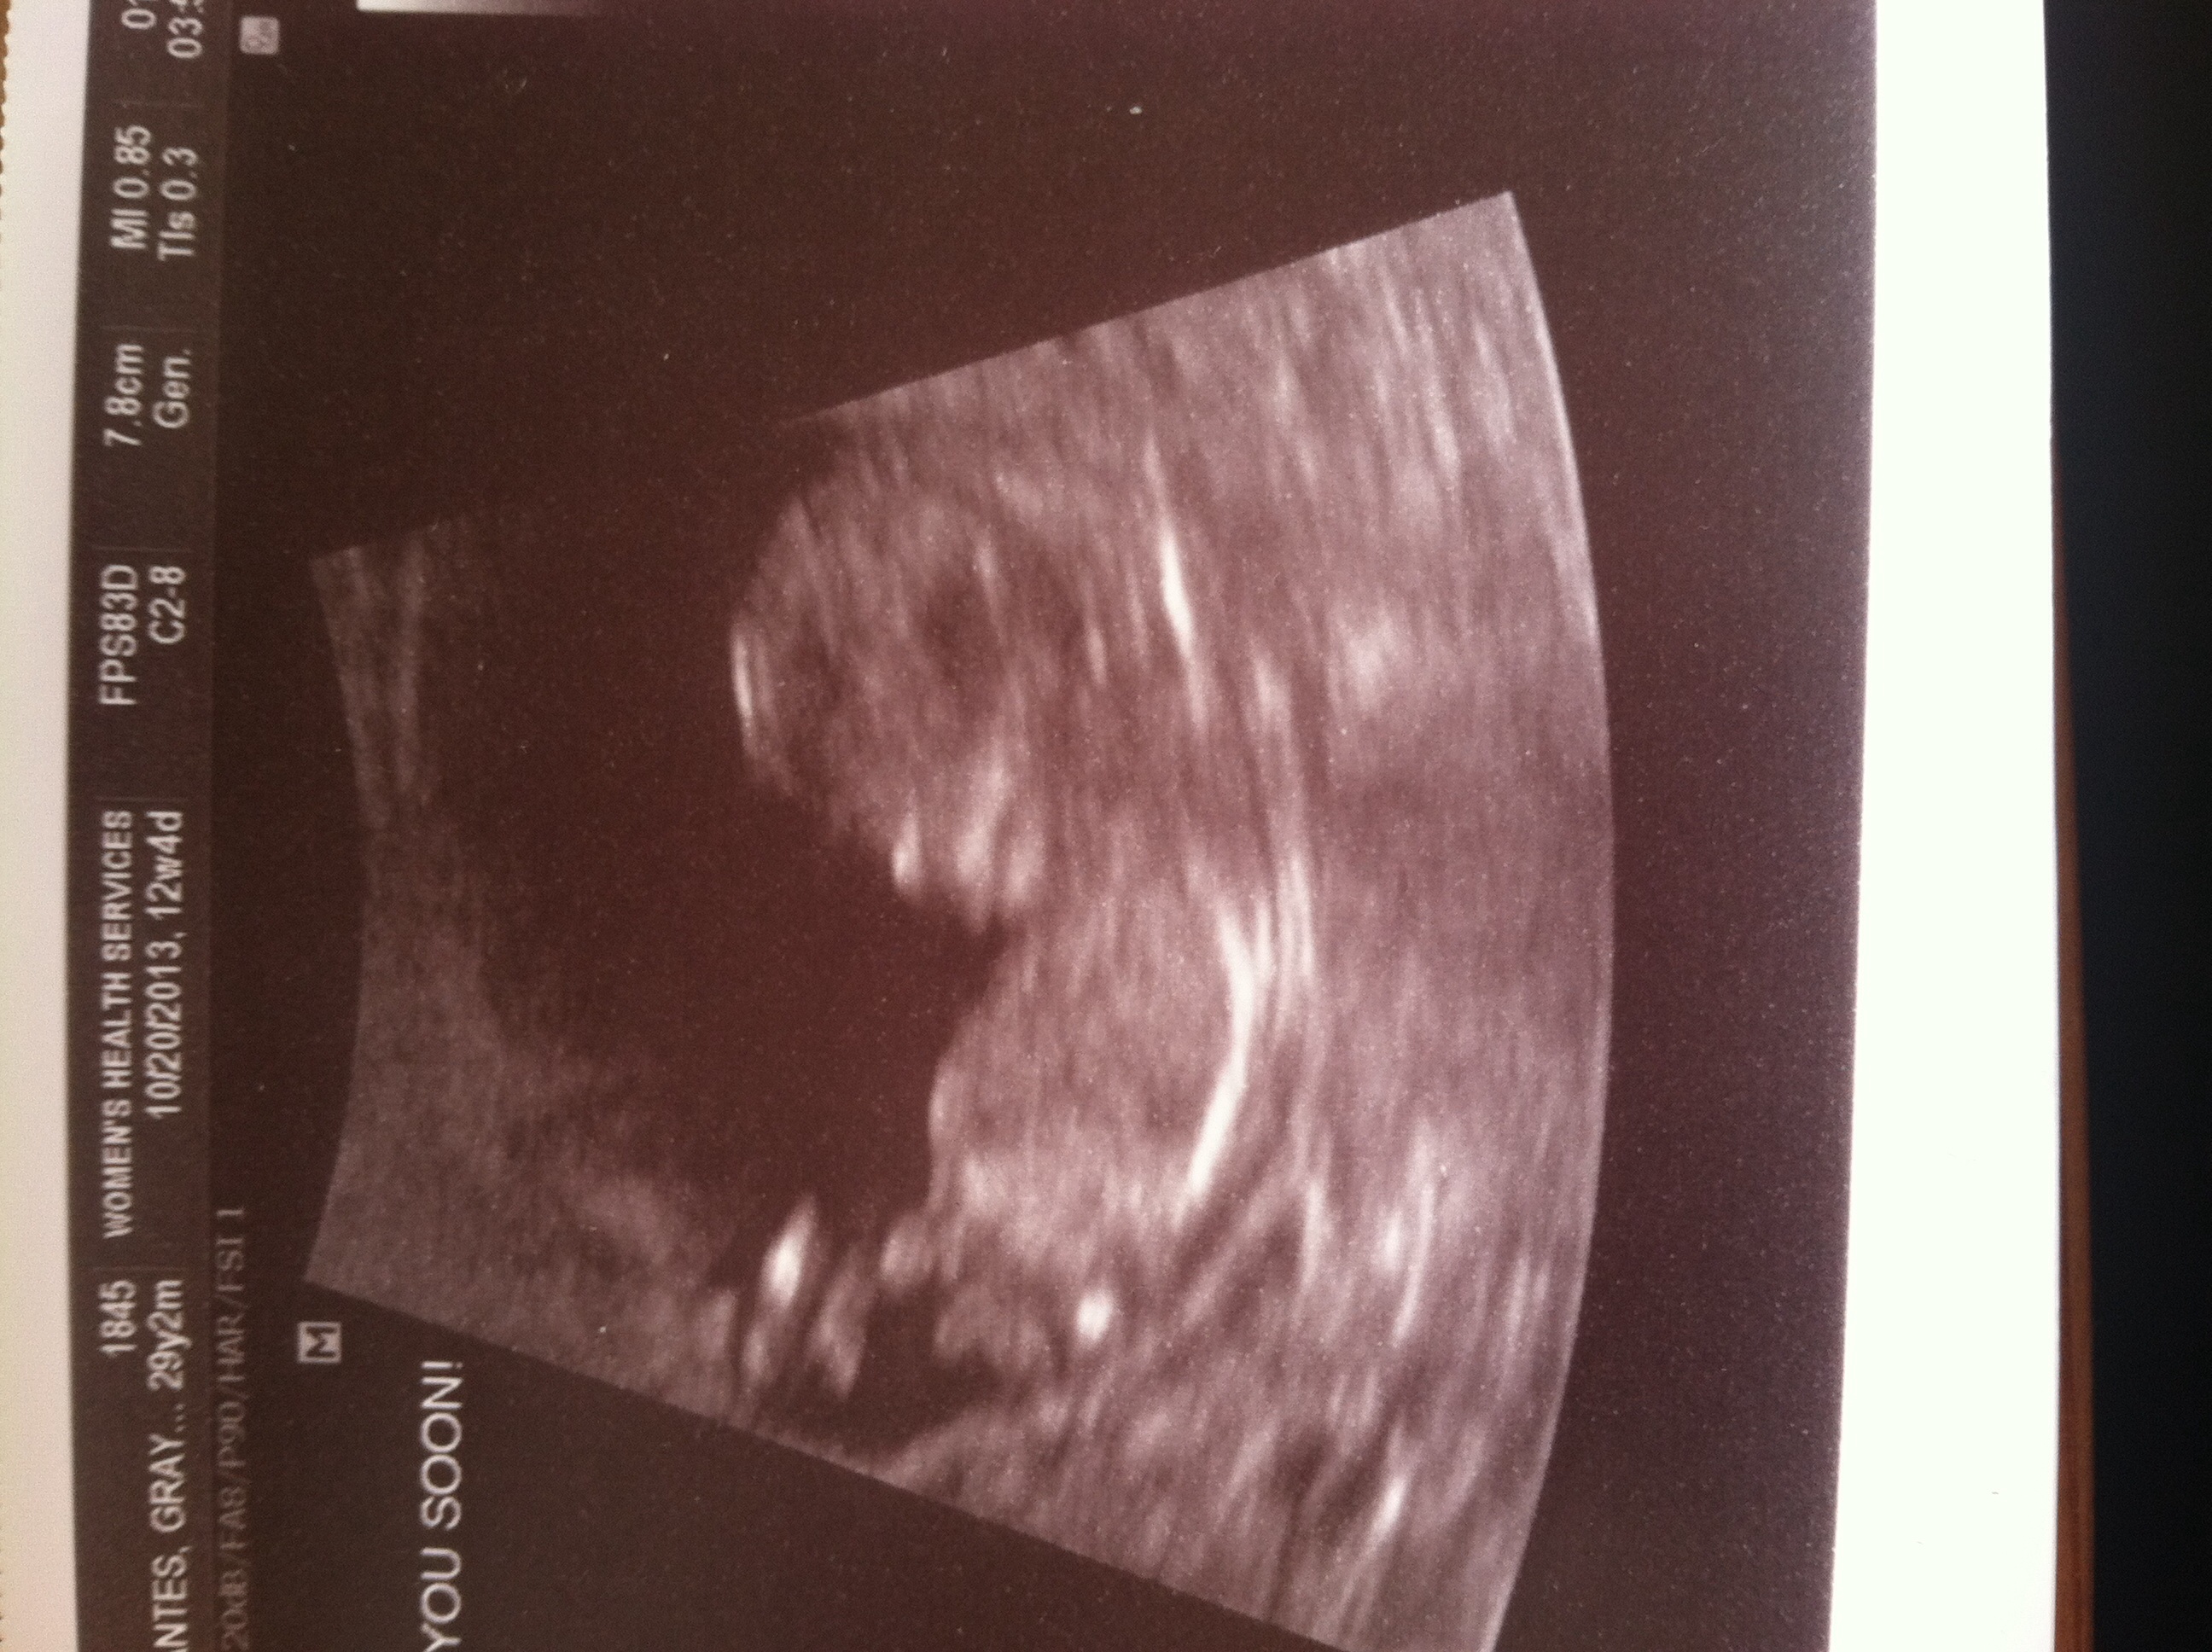

This is my 12 week ultrasound. I would love to see what gender everyone predicts according to the nub or skull theory!Attachment 15411

Quick update! I'm having a girl! Confirmed January 22! So guesses were right!